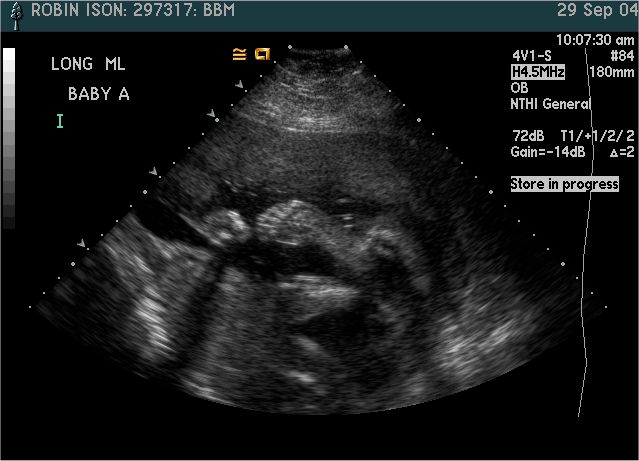

Baby A

Pictures from Ultrasound at 26 weeks.